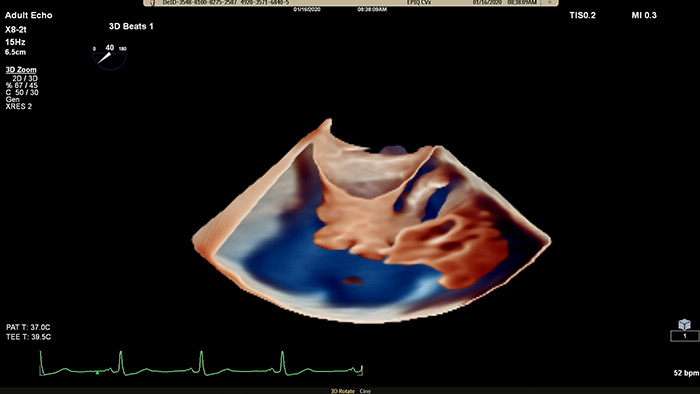

View enhanced visualizations of structures and flow with TrueVue Color

Visualize cardiac morphology using ultrasound with TrueVue Glass